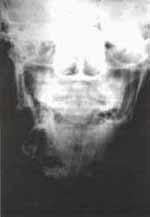

El examen radiológico además de mostrar la localización exacta de la lesión, aporta información acerca de su tamaño, de la reabsorción radicular y desplazamiento de los dientes comprometidos en la lesión. (Fig. No. 3 y 4).

Fig. 3 En proyección PA se observa gran lesión quística que compromete la rama ascendente del maxilar inferior.

Fig. 4 Vista panorámica de un quiste dentígero que compromete bilateralmente las ramas horizontales

del maxilar inferior, observándose marcado desplazamiento de los dientes comprometidos.